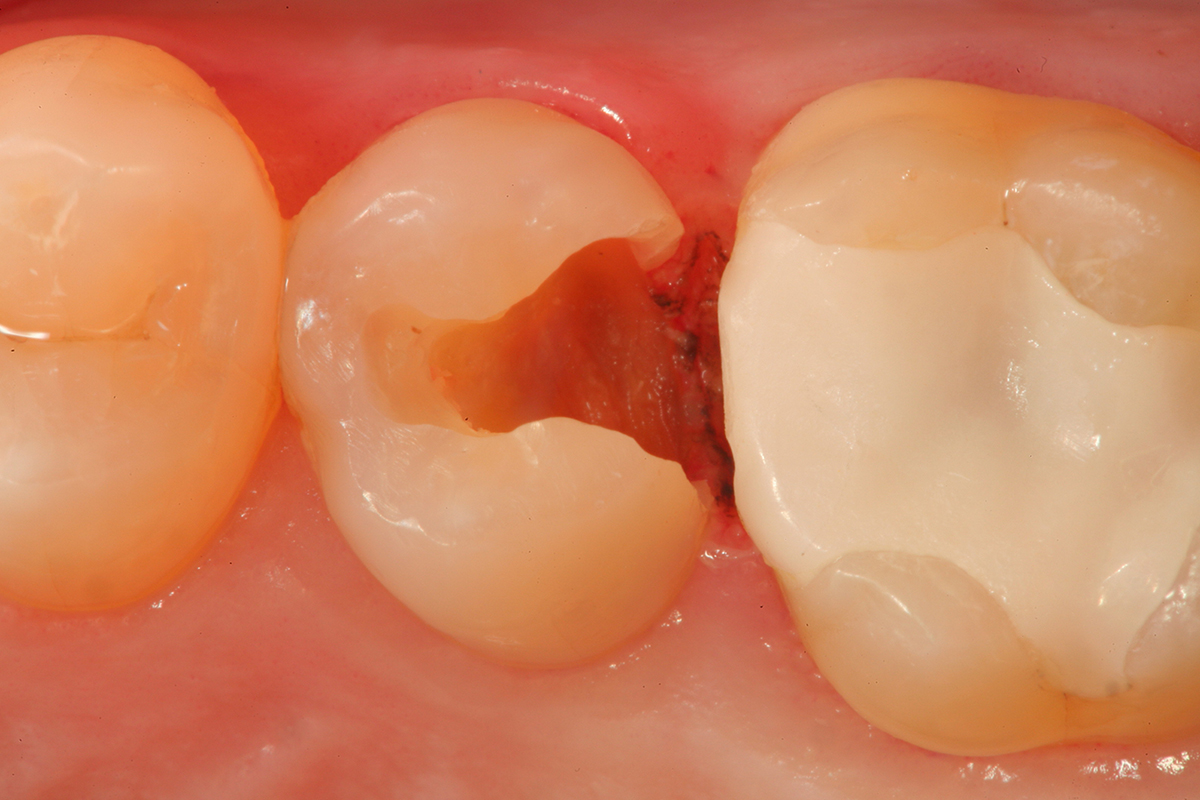

Fig 9. A preoperative occlusal view of teeth Nos. 18 and 19 with composite restorations that are exhibiting marginal breakdown.

Figure 9

Fig 10. After removal of the existing restorations and associated recurrent decay, both cavities are very deep and there is a pinpoint pulpal exposure on tooth No. 19.

Figure 10